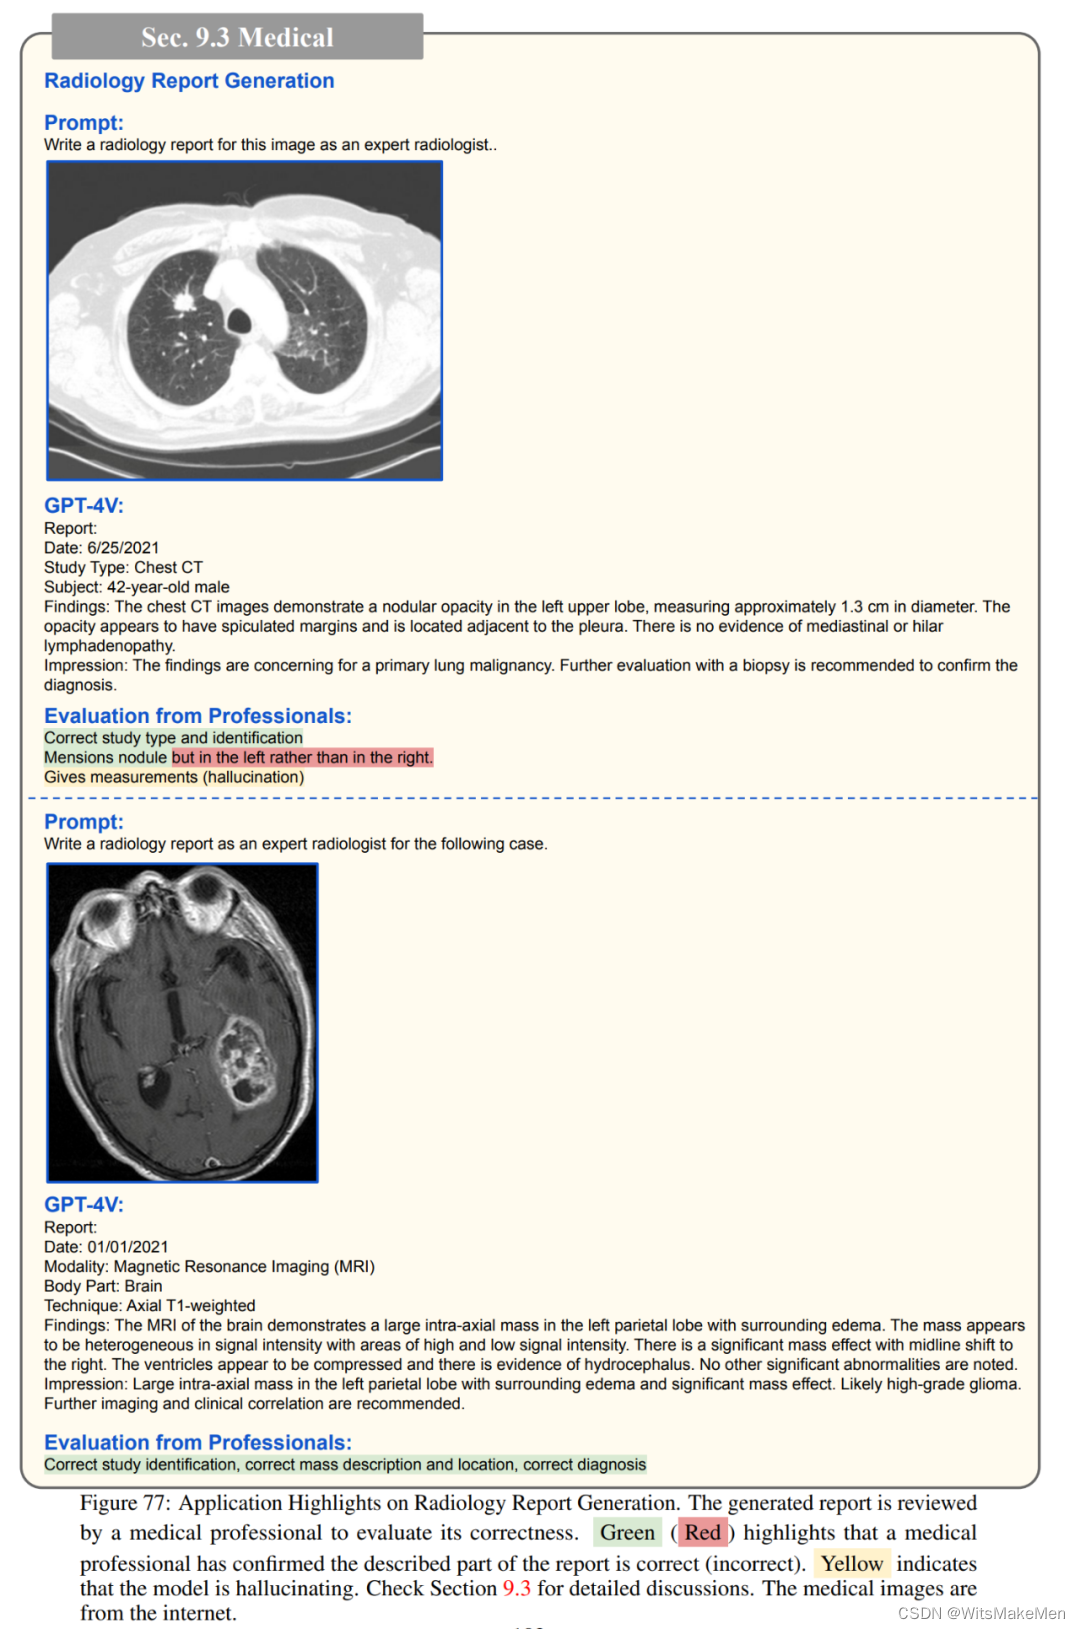

除此以外,GPT-4V还可以识别常见的疾病,例如其能根据肺部的CT扫描指出潜在的问题,又或者对给定的x光片中的牙齿和颌骨,解释下颌左下方和右侧部分出现的智齿可能需要切除;GPT-4V能正确识别徽标,并提供详细的描述,包括其设计,颜色,形状和符号;如果提示中出现的问题与照片不符,GPT-4V也能进行反事实推理。

医药